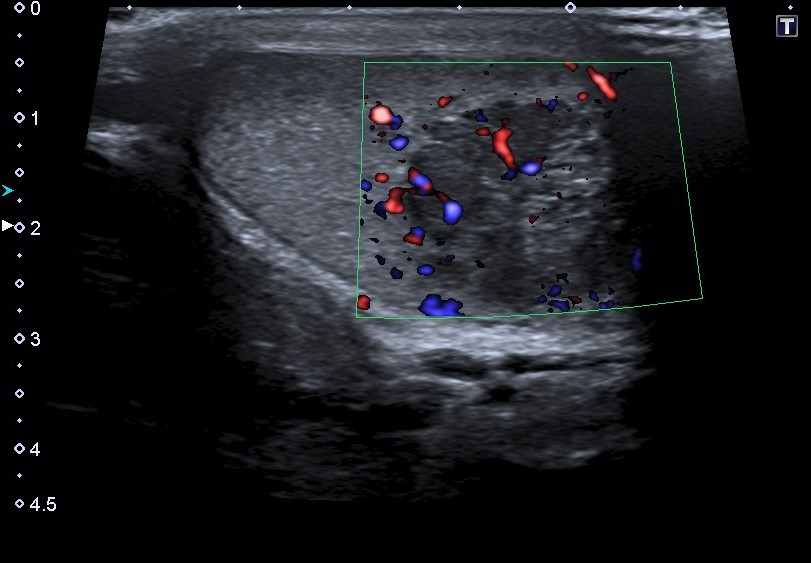

Ecografía escrotal: En testículo derecho se aprecia lesión heterogénea de predominio hipoecogénico con alguna calcificación grosera, polilobulada, de bordes mal definidos, con medidas aproximadas de 36 mm de diámetro máximo, con vascularización en su interior en el registro Doppler, sugestivo de proceso neoformativo testicular. No se objetiva engrosamiento epididimario ni de cubiertas escrotales.